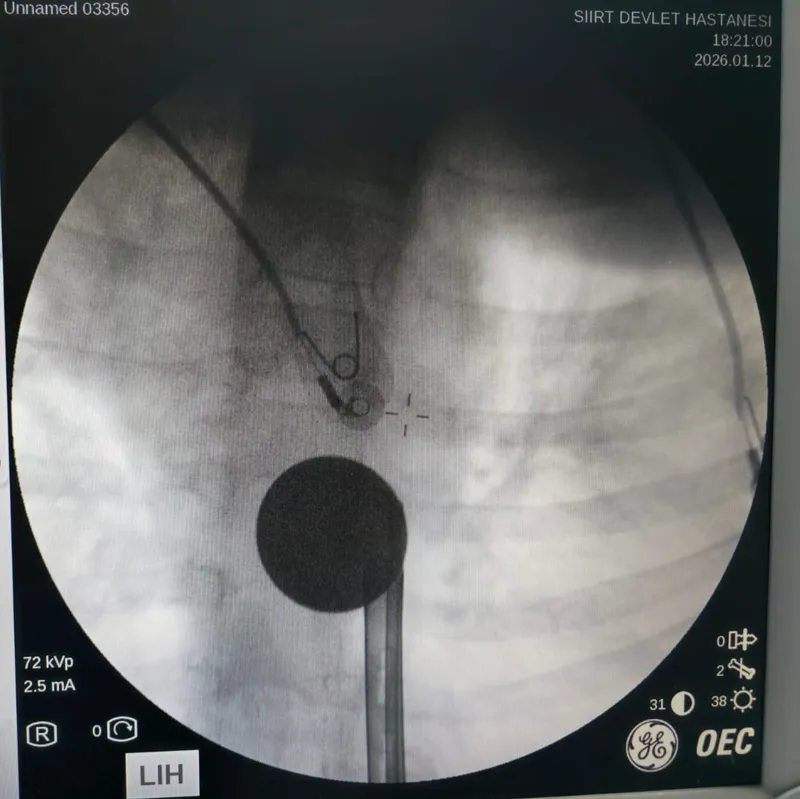

Yabancı cisim yutma şikayetiyle ailesi tarafından Siirt Eğitim ve Araştırma Hastanesine getirilen 8 yaşındaki Y.K., yapılan ilk değerlendirme ve görüntüleme tetkiklerinin ardından ilgili branşlarca operasyona alındı. Y.K.’nın yemek borusuna kadar ilerlediği tespit edilen madeni para, gastroenteroloji uzmanı Dr. Yaren Dirik ve kulak burun boğaz hekimi Yasin Gökçınar tarafından müdahale edilerek çıkartıldı. Operasyonun ardından bir süre gözlem altında tutulan Y.K., tedavisinin tamamlanmasıyla taburcu edildi.

Siirt Eğitim ve Araştırma Hastanesi Başhekim Yardımcısı Uzman Dr. Burak Özkan, çocuk hastalarda yabancı cisim yutma vakalarının ciddi riskler oluşturabileceğini söyledi. Uzm. Dr. Özkan, "Hastanemize başvuran 8 yaşındaki hastamızın yemek borusuna kaçan madeni para, gastroenteroloji ve KBB ekiplerimizin koordineli ve titiz çalışmasıyla herhangi bir komplikasyona yol açmadan başarılı bir şekilde çıkarılmıştır. Operasyon süreci sorunsuz geçmiş olup hastamızın genel durumu iyidir" dedi.